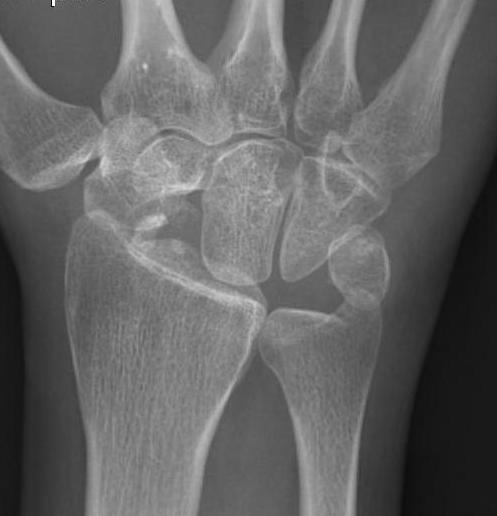

MRI

- comparison of xray and MRI for grading SNAC wrist

- MRI better at detecting carpal OA